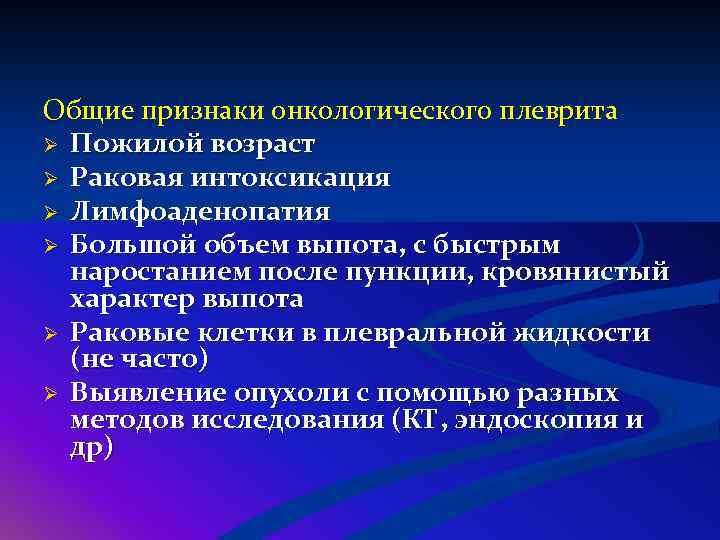

Дифференциальная диагностика заболеваний плевры